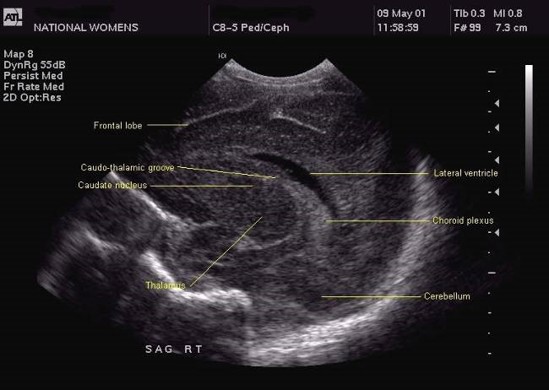

The Ventricular index, as described by Levine, is the absolute distance between the falx and the lateral wall of the anterior horn in the coronal plane at the level of the third ventricle. Values more than 4mm above the 97th centile for gestational age are indicative of significant ventricular dilatation (see chart). A study by Brouwer et al compared early CSF drainage, at a ventricular index of 4 mm above the 97th centile, to drainage beyond this threshold, and showed that early treatment was associated with better development quotient at 2 years and a decreased likelihood of shunt dependence; there was, however, no reduction in the rate of cerebral palsy with early drainage.